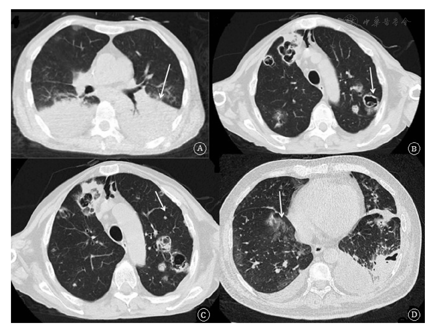

6例患者均行胸部CT检查,5例表现出双肺斑片实变影,5例呈现空洞,3例表现出团块/结节影,3例出现双侧胸腔积液,1例表现出磨玻璃影(图1,表2)。6例患者中2例进行肺穿刺活检,组织标本培养出诺卡菌(图2);2例为肺泡灌洗液培养出诺卡菌;另外2例痰标本培养出诺卡菌(表2)。

注:A. 例6患者胸部CT表现为双肺实变影(箭头所示);B. 例5患者胸部CT表现为多发空洞影(箭头所示);C. 例5患者胸部CT表现为多发结节影(箭头所示);D. 例2患者胸部CT表现出磨玻璃影(箭头所示)和实变影。

肺诺卡菌病患者的影像学表现大多为双侧受累,无明显区域优势[10],可出现实变、多发结节/肿块、空洞、磨玻璃影、胸腔积液、小叶间隔增厚及中央型铺路石征等[11]。Sato等[12]总结的18例肺诺卡菌病患者HRCT表现提示:结节或肿块影占94.4%,磨玻璃影占77.8%,小叶间隔增厚占77.8%,空洞占66.7%。Blackmon等[13]总结的53例肺诺卡菌病患者的CT表现中,实变占64.2%,结节占56.6%,空洞占39.6%,肿块占20.8%。本研究6例患者以实变、空洞、结节/团块影为主要表现,胸腔积液发生率较文献报道稍高。虽然大多数文献中均提示肺诺卡菌病的影像学表现无明显特异性,但与其他常见的机会感染性肺部疾病(病毒、假丝酵母菌、霉菌、结核及耶氏肺孢子菌等)相比,肺诺卡菌病表现出实变范围较大、空洞出现时间较早、磨玻璃影多为小片散在分布等特点,同时,它的空洞常常为多发,非偏心空洞为主,多靠近胸膜处。